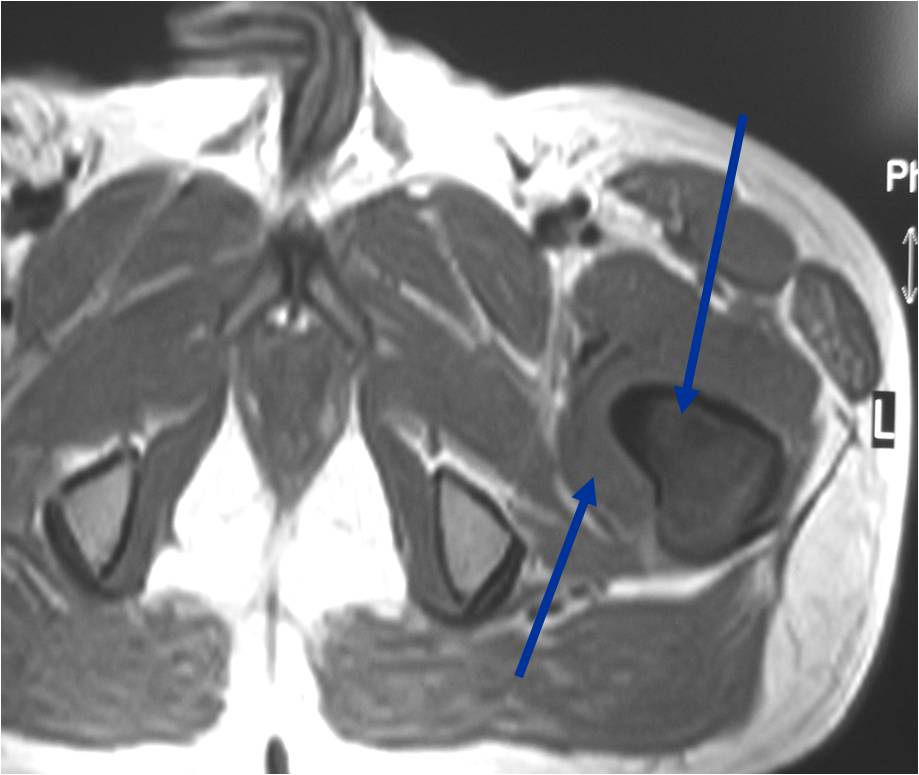

T2 Weighted MRI

TI Weighted MRI